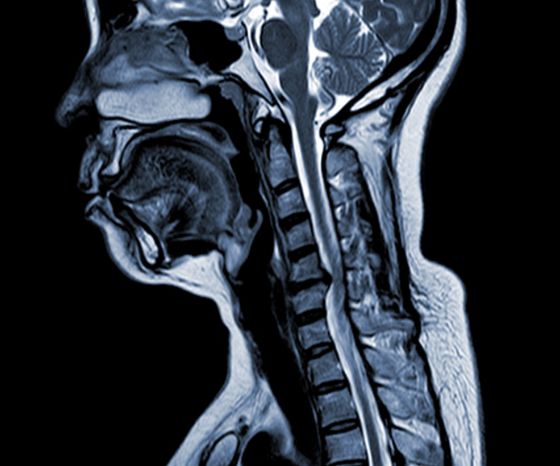

Kohdunkaulan spondyloottinen myelopatia (CSM)

• Keskeisiä tekijöitä ovat välilevyn rappeutuminen, subperiosteaalinen luunmuodostus, takimmaisen pitkittäisliinan luutuminen ja ligamentum flavumin hypertrofia, jotka johtavat selkäydinkanavan puristumiseen ja kaventumiseen.